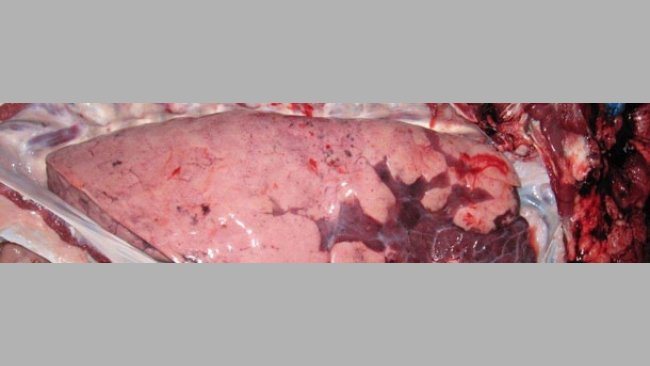

Factores de riesgo asociados a la presencia de lesiones pulmonares y pleuritis en cerdos en matadero